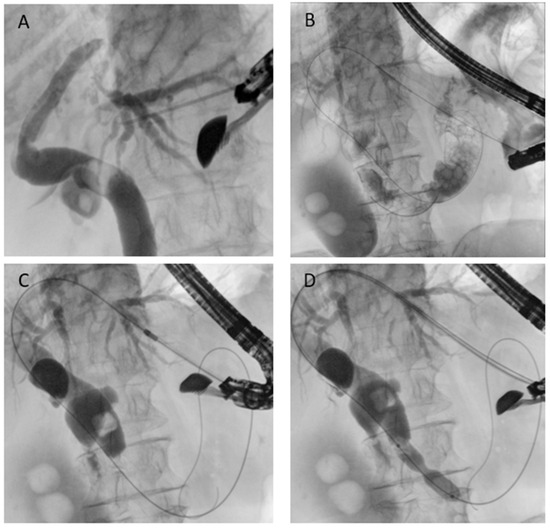

Figure 7. EUS-guided antegrade drainage. (A) Puncture of the intrahepatic duct; (B) guidewire passage into the biliary tree and across the papilla; (C) dilation of the gastric access using a cystotome; (D) endoscopic papillary dilation performed with a biliary balloon dilatation catheter.